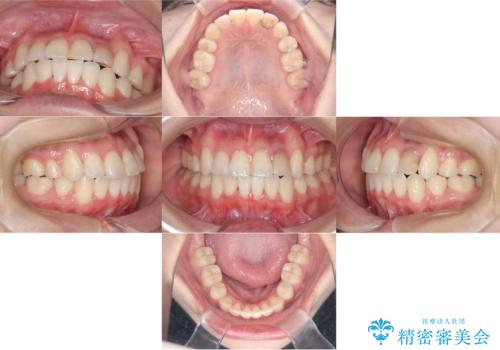

かなり綺麗に並ぶ事ができ大変満足していただけました。

叢生量がかなり多かったのですが、歯肉退縮も失活歯も無くとても綺麗な歯並びになりました。

歯のでこぼこは、歯周病や虫歯のリスクも、とても高いので、見た目のみならず、将来の歯の寿命自体もかなり伸ばす事が出来た治療でした。

歯の寿命を伸ばす為には、歯磨きをし易い環境を作る事がとても大切です。